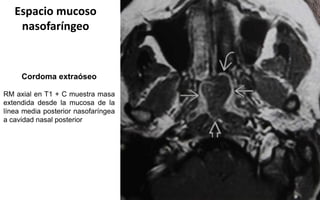

Cordoma extraóseo

RM axial en T1 + C muestra masa

extendida desde la mucosa de la

línea media posterior nasofaríngea

a cavidad nasal posterior